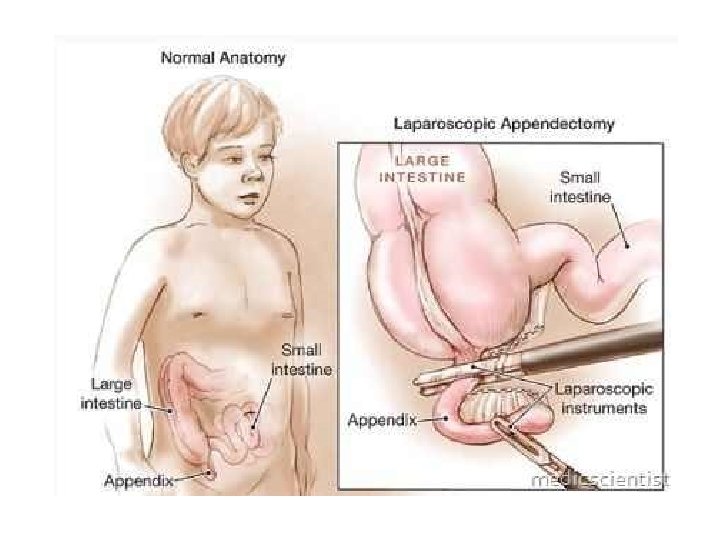

TRAJTIMI: - Hospitalizimi - Monitorimi i parametrave vital - Nuk lejohen analgjezik!!! (sepse maskojne kuadrin klinik) - Antibioterapi iv - Kirurgji: apendektomi e hapur/ laparaskopike